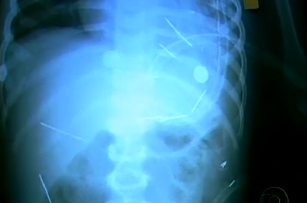

Padrasto espetou cerca de 50 agulhas no corpo de criança de 2 anos

. (Bahia, Brasil)

Haverá um 2010 melhor para ele?

e são estas as radiografias?

diria que não. A impossibilidade técnica é tão evidente que me escuso a comentários

não são fotografias, são imagens retiradas das varias reportagens feitas pela globo.

siga o link